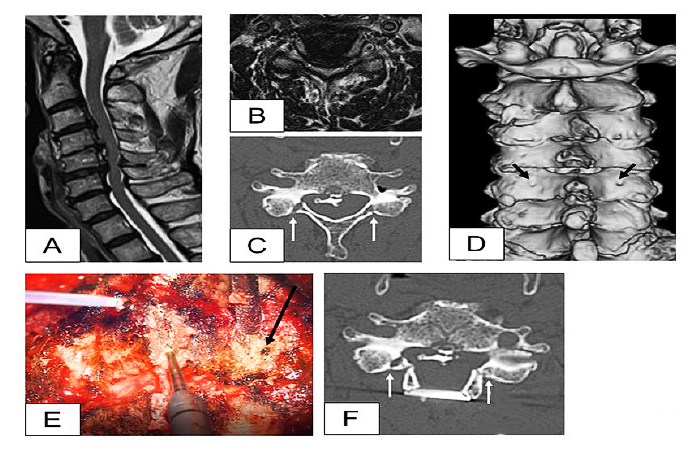

箭头所示为滋养孔的解剖位置

研究发现约1/3的患者存在颈椎滋养孔。C3-C6滋养孔多位于椎管外侧壁约3mm(平均3.06±1.74mm)的椎板后外侧,未发现位于椎管内侧的营养孔。颈椎节段位置越低,滋养孔离椎管越近。

颈椎“双开门”(A-C)和“单开门”(D-F)手术示意图,以滋养孔向内3mm定位进行骨性椎板开槽,可以刚好到达椎管边界

典型病例:脊髓型颈椎病、后纵韧带骨化症,选择颈椎后路双开门减压术。黑色箭头为滋养孔(被认为硬膜外静脉丛的通道,术中根据情况可能需要使用电凝或骨蜡止血),白色箭头是以滋养孔为地标导航,向内3mm制作的门轴处。

因此认为,可以把颈椎椎板后方的滋养孔作为颈椎椎板减压手术的解剖“地标”,在滋养孔内侧3mm处选择“开门”、制作门轴、椎板切除减压是安全可靠的。同时在颈后路脊柱内镜手术中,滋养孔的出现就像夜空中的北极星一样,也可辅助内镜下的辨识定位,避免镜下迷路。